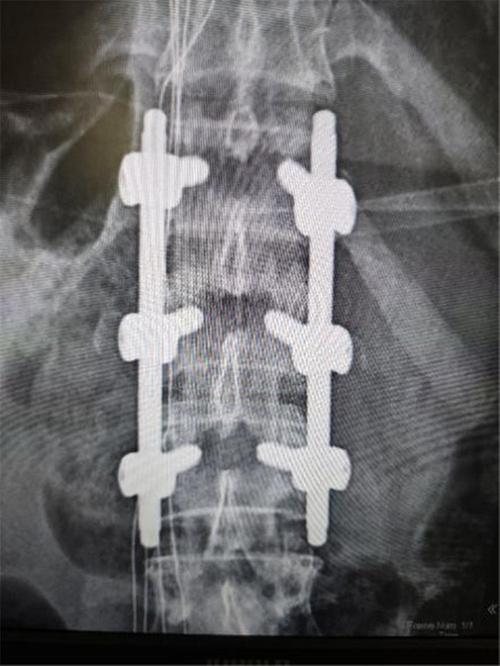

48歲的王女士近日因外傷入院,CT檢查結(jié)果顯示腰1椎體爆裂骨折,骨折累及前中柱,椎體后壁骨折塊突入椎管,壓迫硬膜囊??剖壹怪鶊F隊經(jīng)過深入討論,一致認(rèn)為該患者骨折屬于不穩(wěn)定性,若不及時治療,有極高的癱瘓風(fēng)險,應(yīng)盡量采用創(chuàng)傷較小術(shù)式早期手術(shù)結(jié)合術(shù)中椎管造影確保手術(shù)效果。

在骨科與手麻科團隊的緊密配合下,首次采用肌間隙入路技術(shù)成功為患者實施了手術(shù)治療。這一技術(shù)相較于傳統(tǒng)的后正中入路,利用多裂肌和豎脊肌之間的天然間隙,減少了對肌肉的牽拉,避免了腰背肌的醫(yī)源性損傷或壞死。術(shù)中出血量顯著減少,僅為80ml,遠低于傳統(tǒng)手術(shù)的200~300ml。術(shù)后,患者清醒且未出現(xiàn)腰痛、腰脹等不適癥狀。